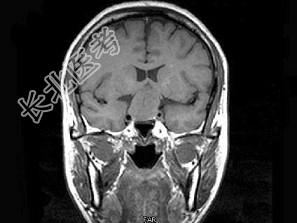

- 单项选择题男,49岁, 1年前发现双颞侧视野缺损,视物模糊, 查体:双颞侧偏盲, 根据所提供图像,最可能的诊断为 ( )

A、垂体微腺瘤

B、颅咽管瘤

C、脑膜瘤

D、嫌色细胞腺瘤

E、生殖细胞瘤